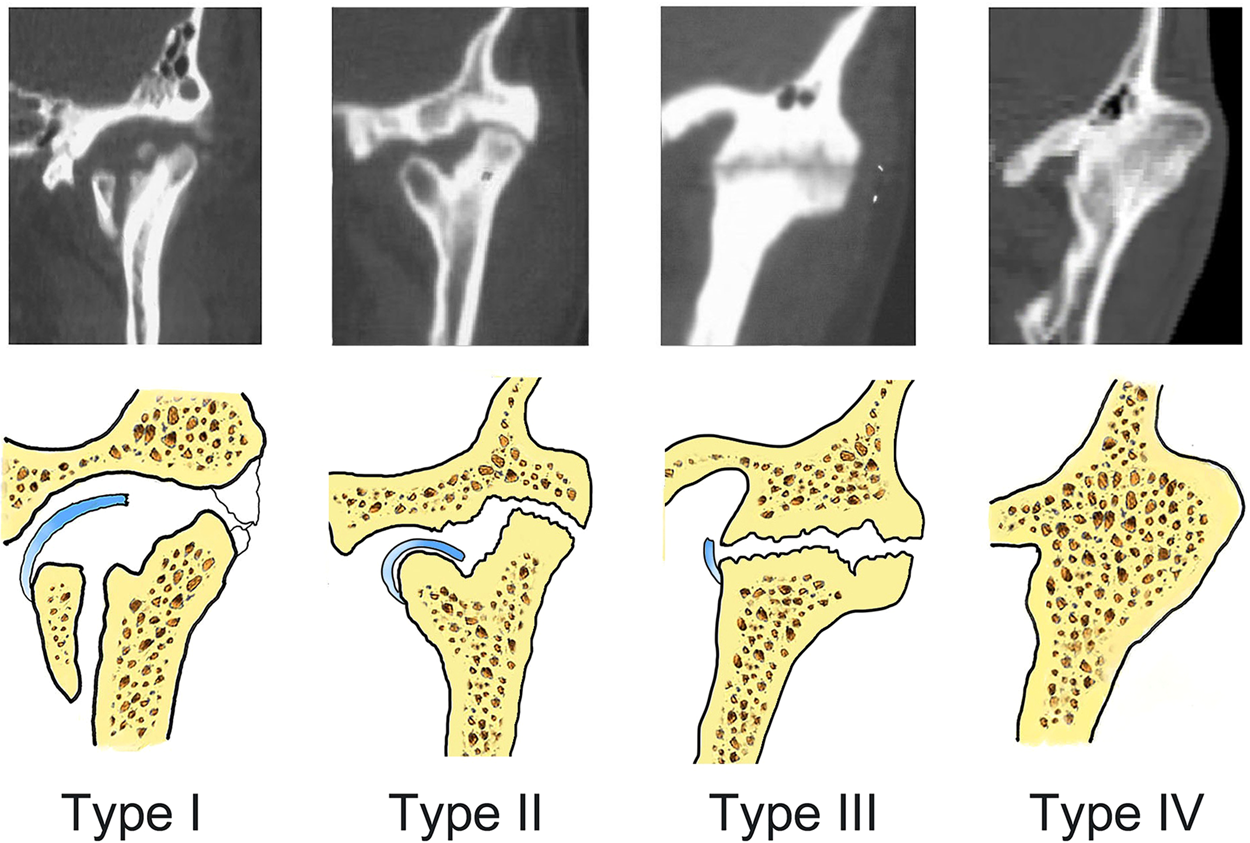

Figure 1

Computed tomography images and representations of the four types of temporomandibular joint ankylosis. Type I is nonbony ankylosis of the joint, with the fossa and condyle clearly seen but with scattered callus. Type II is lateral bony ankylosis of the joint, with bony fusion on the lateral side of the joint. The medially displaced condyle, residual disc, and fossa form a pseudarthrosis. Type III is complete bony ankylosis of the entire joint with a radiolucent line inside the fusion area but no recognizable condyle and fossa. Type IV is extensive bony ankylosis, with complete disappearance of the joint and with no radiolucent line.